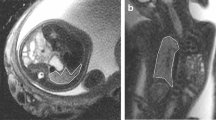

These developmental changes of lung structure can be visualized by ultrasound and MRI. According to the decrease in tissue density, especially during the canalicular and saccular stages of lung development, the sonographic appearance of the fetal lung parallels this process by changes in the lung tissue echogenicity. At 22 and 23 GW, the mean gray value of the fetal lung on T2-weighted and T1-weighted sequences equals that of the fetal liver (Fig. 2). Between 24 and 31 GW, the lungs linearly become darker and less echogenic, and finally, increase in echogenicity in the last weeks before birth (Tekesin et al. 2004). However, no single sonographic feature has been found to significantly correlate with the biochemical maturity of the fetal lung (Cayea et al. 1985).

Axial T2-weighted sequences of the fetal thorax, at the level of the tracheal bifurcation at 15 (a), 21 (b), 25 (c), and 31 (d) GW. Note the initial intermediate signal intensity of the fetal lung, decreasing during the canalicular stage with the lowest signal intensity between 19 and 23 GW (b). Afterwards, the T2-weighted signal increases substantially

At the beginning of the canalicular stage (17 GW), the fetal lung is visualized by T2-weighted sequences with an intermediate signal intensity, modestly hypointense to amniotic fluid and clearly hyperintense to muscle and to liver (Figs. 2–4). Using T2-weighted sequences, the anatomy of the lungs, grossly showing their characteristic morphological organ shape, the trachea and hilar structures, which are mostly fluid-filled at this stage, are successfully visualized (Figs. 5–7). Occasionally and inconsistently, the fluid-filled esophagus can be seen as well as fluid-filled structure, especially at the level of the hiatus (Fig. 5).

Comparative scheme of axial T2-weighted and balanced gradient echo sequences in the visualization of the fetal thorax at 21 GW: the fetal respiratory tract is visualized from laryngeal level (black arrowheads) to the tracheal bifurcation (white arrow) and the fluid-filled main bronchi. The esophagus can be frequently seen on T2-weighted sequences at the level of the hiatus (circle). Note the less clear delineation between lung and liver tissue on balanced gradient echo sequences

Whereas T1-weighted sequences are less efficient in depicting the pulmonary anatomy, they initially provide a stable, intermediate signal intensity of the pulmonary tissue (Figs. 3, 4, and 6). These imaging characteristics may be related to the high amount of protein and lipid rich interstitial mesenchyme and the comparably low amount of free intraluminal lung fluid.

It is commonly accepted that the brightness of the fetal lung parenchyma on T2-weighted sequences increases with gestational age (Duncan et al. 1999a, b; Kuwashima et al. 2001; Levine et al. 2003; Balassy et al. 2004; Keller et al. 2004; Osada et al. 2004; Brewerton et al. 2005). This effect can be detected at different echo times, but its visual perception is greatest using echo times longer than 120 ms (Fig. 2) (Balassy et al. 2007).

T1-weighted sequences can often be successfully acquired during maternal breath hold providing a robust signal, which can be most consistently quantified. It has been concordantly demonstrated that the T1-weighted signal of the fetal lung is declining during the canalicular and saccular stage of lung growth (between 20 and 30 GW, Figs. 3, 4, and 6) (Duncan et al. 1999a, b; Balassy et al. 2007).

Before birth, the fetal lung displays a very characteristic homogenous bright appearance on T2-weighted images and profound hypointensity on T1-weighted sequences.